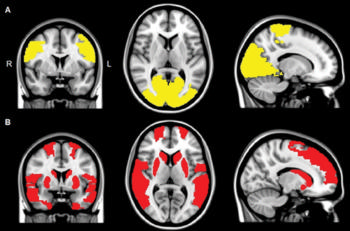

Figure 2. MR images show reduced regional functional connectivity in, A, Parkinson’s disease (PD) patients and, B, exclusively in PD + visual hallucinations (VH) patients. Regional functional connectivity analysis revealed lower functional connectivity in PD + VH as well as PD – VH patients compared with control participants in paracentral and occipital regions (yellow areas in A; P < .05, corrected for multiple comparisons). Functional connectivity in frontal, temporal, and subcortical regions was exclusively lower in patients with PD + VH compared with control participants (red areas in B; P < .05, corrected for multiple comparisons).